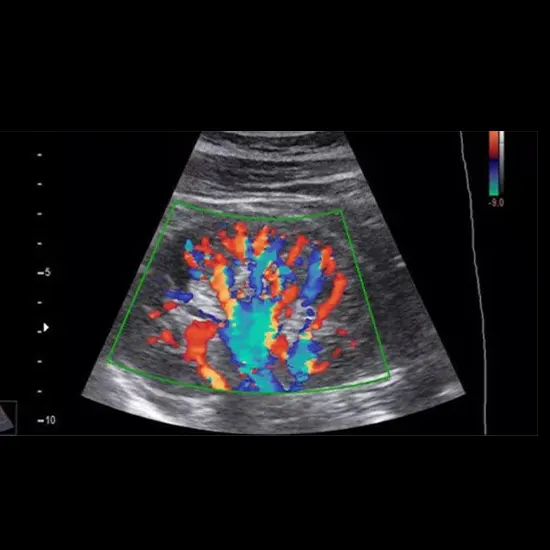

- Advanced equipment and technology: As per NABH accreditation guidelines, our ultrasound center uses advanced equipment and technology, ensuring that patients receive the latest and most accurate imaging services.